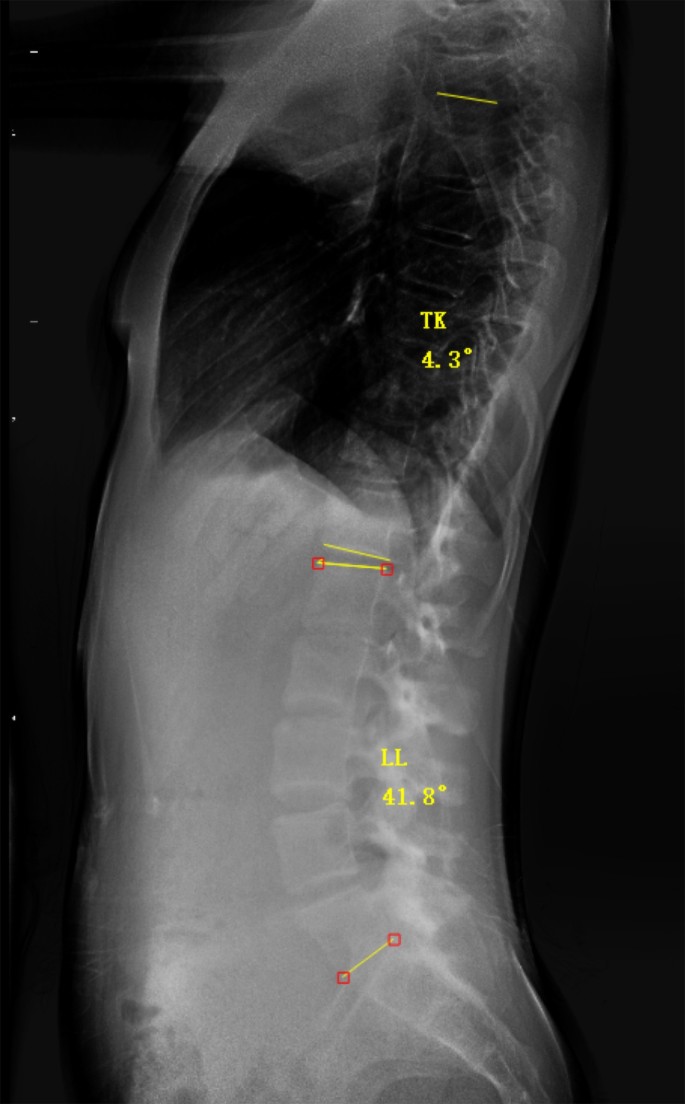

In the 102 AIS patients who also underwent full-length lateral spine X-rays, TK and LL were measured using the following method (Fig. 2): (1) TK: the angle between the extension lines of the upper border of T5 and the lower border of T12 vertebra; (2) LL: the angle between the extension lines of the upper border of L1 and the lower border of L5 vertebra.